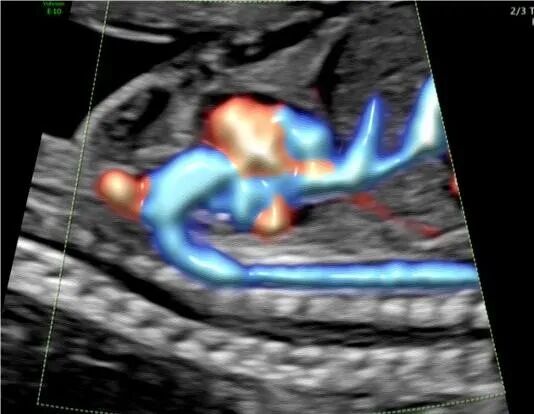

六、煊流成像技术

不仅得到了三维血管栩栩如生的显示,更是在微小血管成像上更加敏锐、可靠。可真实呈现胎心结构、脐带、血流变化,提升产前检查的诊断质量和效率。